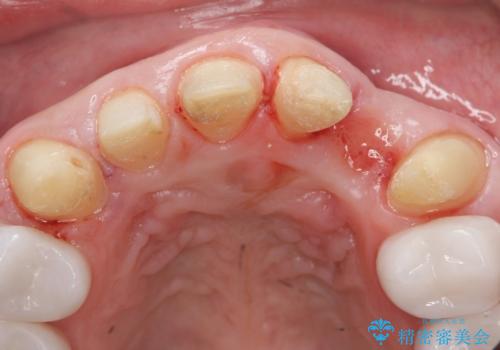

歯頚ラインが変えられないことや天然歯を削るリスクをご理解頂いた上で、オールセラミッククラウンによる補綴治療を行いました。(見えない奥歯のみ天然歯のままとしました)

それ以外の歯は神経をとらずに済むよう、慎重かつ丁寧に歯の形態を整えました。

矯正治療で歯並びを整えたいというのが歯科医師である私の本心でしたが、患者様の強いご希望によりオールセラミッククラウンによる補綴治療を行いました。

クラウンの色味に関して、自然な白さ(シェードA1~NW0.5)のクラウンを作製・試適したところ「もっと白くしたい」と希望され、当院で最も明度の高い色(シェードNW0)に修正しました。

被せ物の種類:オールセラミッククラウン スタンダード (シェード:NW0)